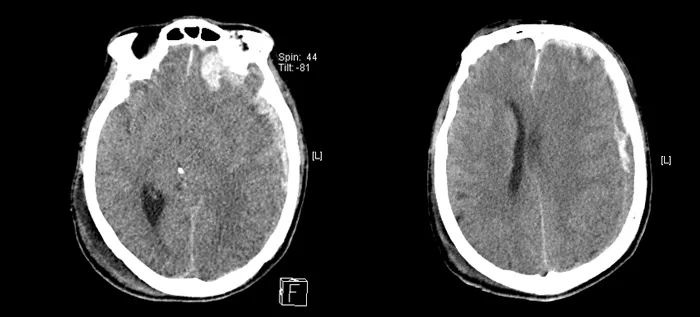

頭顱CT提示

左側(cè)額顳頂部硬膜下血腫

左側(cè)顳葉腦挫裂傷

枕骨右側(cè)骨折

右側(cè)眼球萎縮鈣化